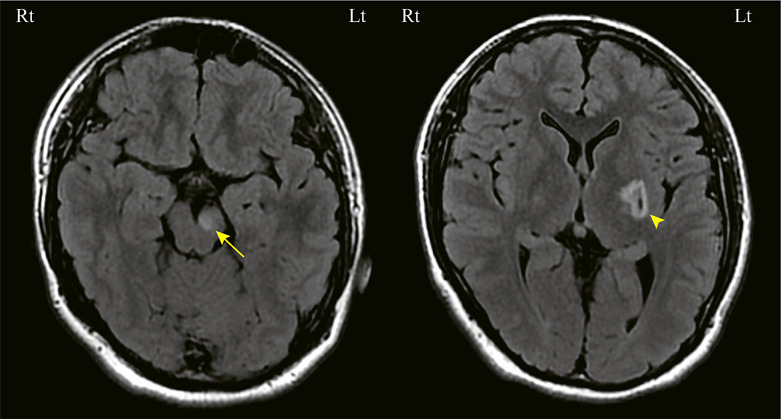

Case presentation: An 18-year-old male patient developed symptoms of dystonia at the age of 15 years. Two years later, he noticed decreased visual acuity and central scotoma in the left eye. One month later, the same symptoms occurred in the right eye. Although the optic discs in both eyes revealed mildly redness and edematous change, no abnormal findings were detected on fluorescence fundus angiography and orbital magnetic resonance imaging. Mitochondrial deoxyribonucleic acid (mtDNA) sequencing detected the m.14487 T>C mutation. From clinical course and fundus findings, the case was diagnosed LHON. The optic nerve gradually atrophied and central scotoma remained.